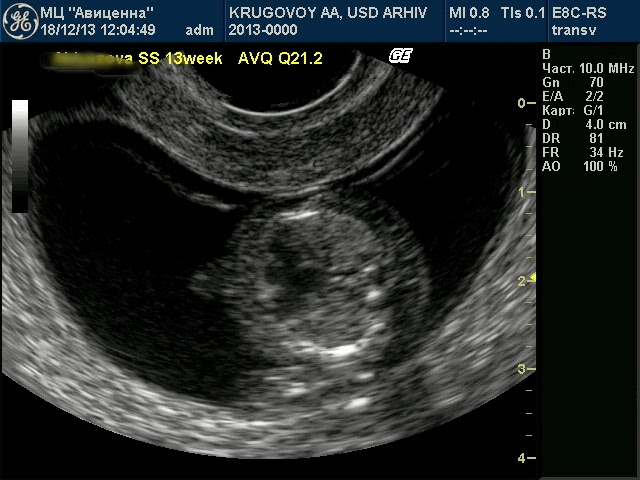

Случай пренатальной диагностики атриовентрикулярной коммуникации в 13 недель беременности.

Очень раритетный случай. Сегодня случайно (?) удалось диагностировать грубейший порок сердца уже в 13 недель беременности. Формально - это АВК (Q21.2), но на самом деле - сердце представлено одной большой камерой с какими-то намеками на перегородки. Типа такие отростки не пойми для чего.

Чтобы было понятно, то размер сердца на фото примерно 7 мм.